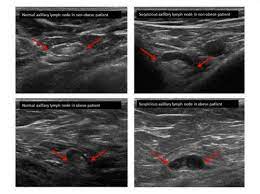

On ultrasound it will be hypoechoic with spiculations radiating away from the nipple. Radiographic features ultrasound malignant characteristics (with positive predictive values) Ultrasound imaging allows better evaluation of the status of the axillary lymph nodes in patients with ibc, an important step in determining extent of disease prior to initiation of chemotherapy. Is the abnormal enlargement of rudimentary male breast tissue. You might get a breast ultrasound: Breast cancer is among the most common causes of cancer deaths today, coming fifth after lung, stomach, liver and colon cancers. Many cancers are not visible on ultrasound. Breast cancer usually makes or presents as a mass or tumor or a lump. This type of cancer also changes the appearance of your breasts. Papillary dcis, a special variant, will show up as matter within the ducts, like a clog within a pipe. It is the most common cause of cancer death in women. in 2005 alone, 519 000 deaths were recorded due to breast cancer. this means that one in every 100 deaths worldwide and almost one in every 15 cancer deaths were due to breast cancer. Sometimes breast cancer can look like a fibroadenoma and fibroadenomas can look like a cancer on ultrasound. Many calcifications seen on mammography cannot be seen on ultrasound.

On the flip side, there are benign (not cancerous) breast changes which can mimic breast cancer as well. This type of cancer also changes the appearance of your breasts. If you're younger than 25. Is the abnormal enlargement of rudimentary male breast tissue. Ultrasound imaging allows better evaluation of the status of the axillary lymph nodes in patients with ibc, an important step in determining extent of disease prior to initiation of chemotherapy.